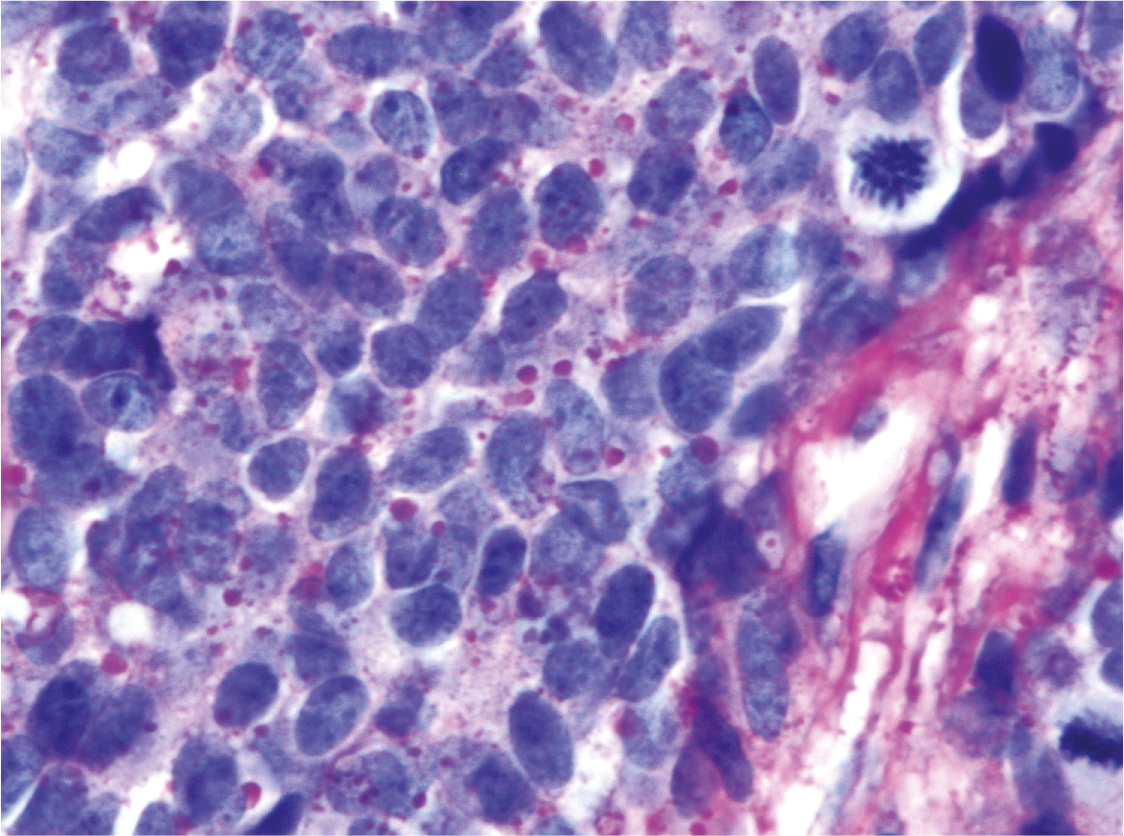

Fig 1

Figure 1. Blue cell tumor. The microphotograph depicts a resection specimen of the lung showing a “round” blue cell tumor involving the right lower half portion of the picture (dark blue area). The tumor is well demarcated and the intensity of the tumor cells is identifiable easily comparing to the alveolar parenchyma of the lung of the left upper half of the picture. The “roundness” of the tumor cells with round-ovoid contour is not appreciable at this magnification, but is better identifiable in figure 2 (Hematoxylin and Eosin staining x 12.5 original magnification).